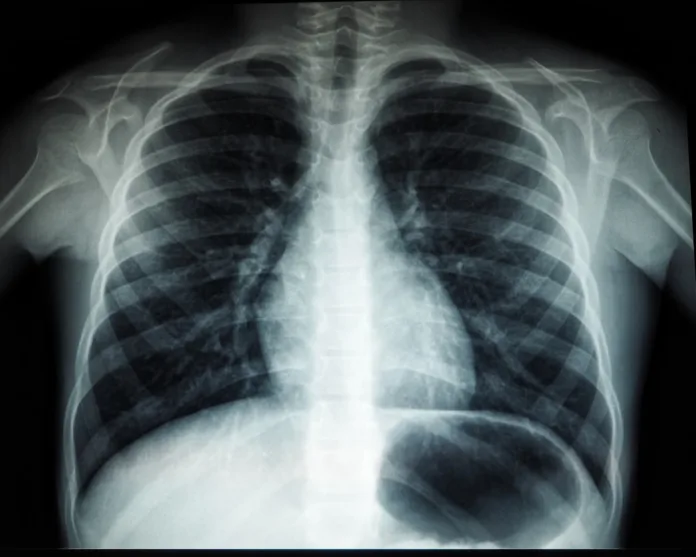

Клиника Helios в Крефельде установила один из десяти существующих в Германии навигационных бронхоскопов. Как сообщает RP Online, это устройство с поддержкой искусственного интеллекта помогает врачам находить даже самые маленькие опухоли в труднодоступных участках лёгких. Важно, что во многих случаях новая технология позволяет взять анализ тканей без хирургического вмешательства, делая диагностику более щадящей для пациента.

По словам врачей, этот аппарат «меняет правила игры» в раннем выявлении онкологических заболеваний. Центр по лечению заболеваний лёгких в Крефельде стал одним из немногих в стране, где пациенты могут пройти такое передовое обследование. Это значительно повышает шансы на своевременное обнаружение болезни и успешное лечение для жителей региона.